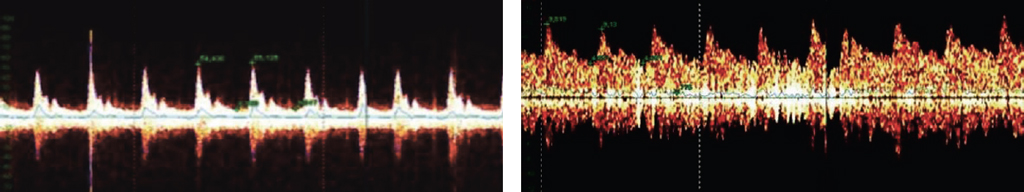

В проекции наружного отверстия пахового канала производили разрез кожи длиной 2–2,5 см. С помощью ранорасширительных крючков кожу смещали в сторону внутреннего отверстия пахового канала и корня полового члена. В операционной ране выделяли все сосудистые структуры семенного канатика, включая варикозно-измененные вены. Всем пациентам группы 1 во время операции производили сканирование сосудистых структур семенного канатика допплерографическим датчиком с частотой 10 МГц на аппарате «Минимакс Допплер К» (Россия). Определяли кровоток, который отражался на экране монитора и сопровождался звуковыми сигналами (рис. 1). Если ультразвуковой датчик был расположен в зоне артерии, то отмечали ритмичный пульсирующий звуковой сигнал в разных тональностях, если над венозным сосудом — непрерывный шумовой сигнал в одной тональности, похожий на «шум ветра». В зависимости от полученных визуальных данных и звуковых сигналов, характеризующих тип кровотока, в семенном канатике дифференцировали венозные сосудистые стволы от артериальных. Дальнейший ход операции не отличался у пациентов обеих групп. Варикозно-расширенные вены выделяли, лигировали и пересекали. Оболочки семенного канатика, подкожную жировую клетчатку и кожу послойно ушивали однорядными узловыми швами. Во время выполнения операции подсчитывали количество идентифицированных венозных и артериальных стволов, а также продолжительность оперативного вмешательства.

Рис. 1. Допплерографическое отображение артериального (а) и венозного (b) типов кровотока (https://minimax.ru/articles/surgery/use-of-intraoperative-doppler-minimax-k.html)